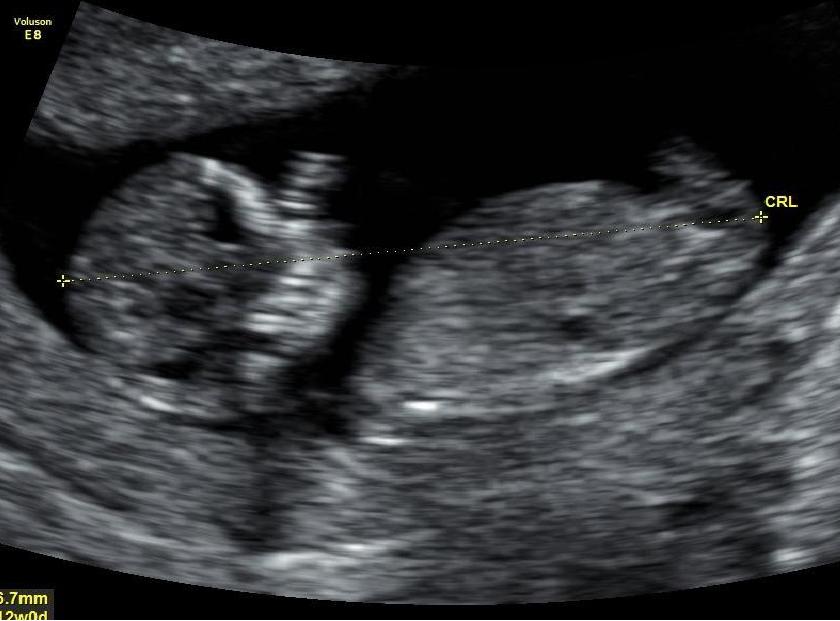

Please can the nub experts let me know if im having a boy or girl please :) Thank you so much

No nub :(

IF what I can see is a nub, and I'm not sure as it's not a clear picture, I would say girl. But not too easy to guess from the picture.

I only see a whisper of a nub in the bottom pic and it's probably not completely captured. Sorry!